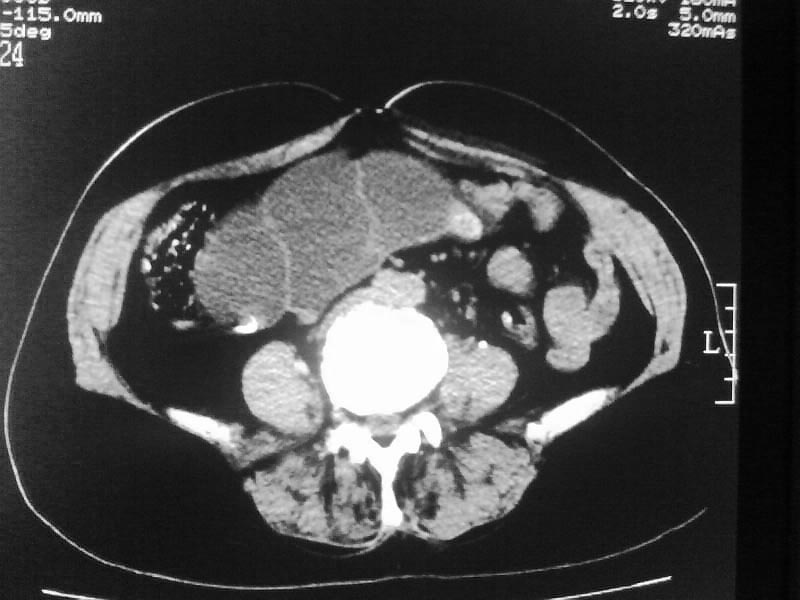

标题: CT20044:女,45岁,腰痛2年,双肾结石,右输尿管结石,右肾重度积 [打印本页]

标题: CT20044:女,45岁,腰痛2年,双肾结石,右输尿管结石,右肾重度积

加扫下输尿管和膀胱吧,先排除下面的大结石所致的积水;

再排除下面的压迫性病灶;

支持双肾结石、右输尿管上端结石,右肾重度积水

双肾结石、双输尿管结石并右肾积水。